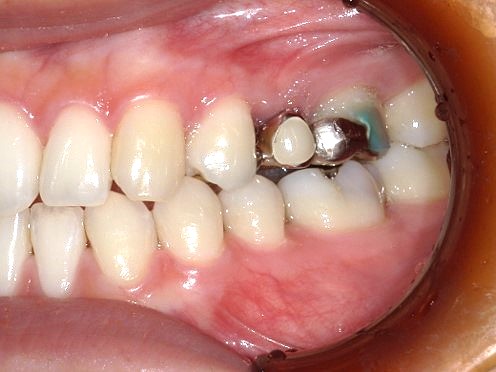

保険適応の銀歯の見た目が気になるので白く治したいと来院されたケースです。

笑ったときに口角があがると側面にある銀歯が光って見えるとご家族の方に言われて気になるようになって白くしたいと思うようになったそうです。

【主訴】左上の銀歯を白く綺麗に治したい

【治療内容】左上ジルコニアセラミッククラウン修復

【治療回数】3回